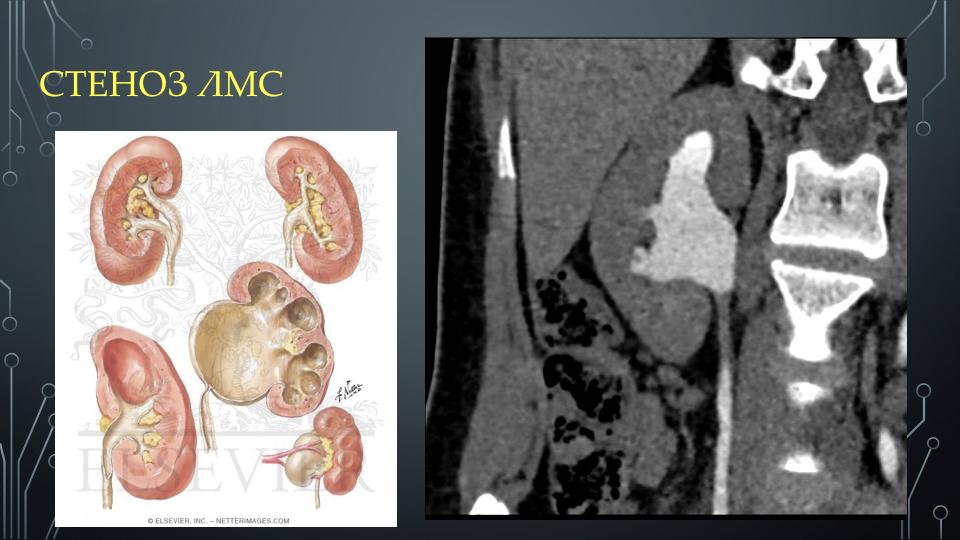

Интраренальная лоханка: рентгеновские снимки и примеры

Раздел: Фотоэссе